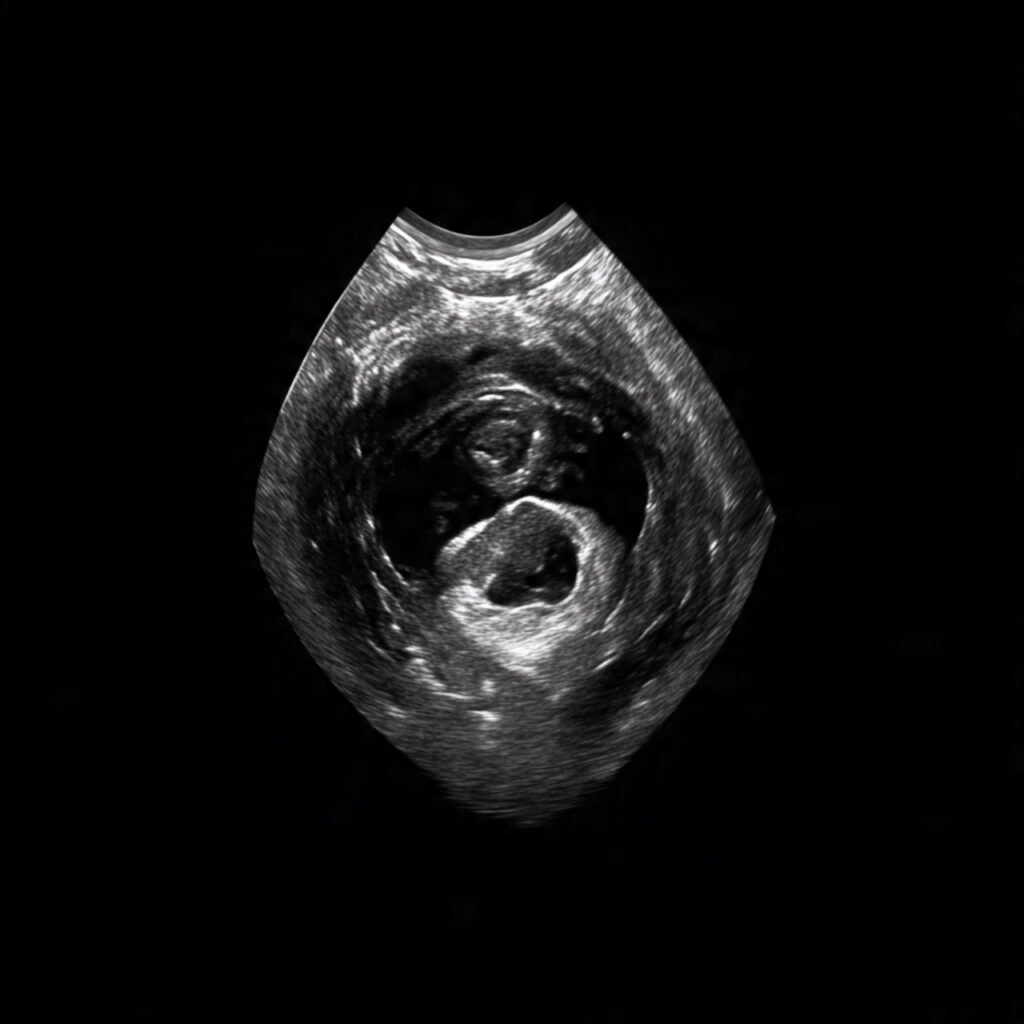

Founder of Nisarga Diagnostics, is a renowned fetal ultrasound specialist with over 20 years of expertise. An alumnus of Government Medical Colleges in Mysore and Bangalore, he also holds a D.N.B. from the National Board of Examinations, Delhi, and certification from the Fetal Medicine Foundation, London. A former Professor and HOD, he has trained countless PG students and junior radiologists, shaping the future of fetal imaging in India.